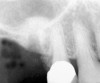

First, a periapical radiograph is taken to determine the amount of bone subantrally. It should be noted that a periapical film has an average error of 14%.23 Therefore, it is advantageous to take the radiograph in a manner that includes a marker (5-mm wide ball bearing) in order to be able to calculate the magnitude of radiographic error (Figure 1).

Figure 1  At tooth site No. 14, a periapical radiograph was taken with the long-cone paralleling technique. The radiographic ball marker measured 5.8 mm while its actual diameter is 5 mm. The enlargement is 0.8 mm, therefore the magnification error is 0.8/5 = 16%. By correcting for this error, a closer approximation of the amount of bone from the osseous crest to the sinus floor can be made.

Figure 1